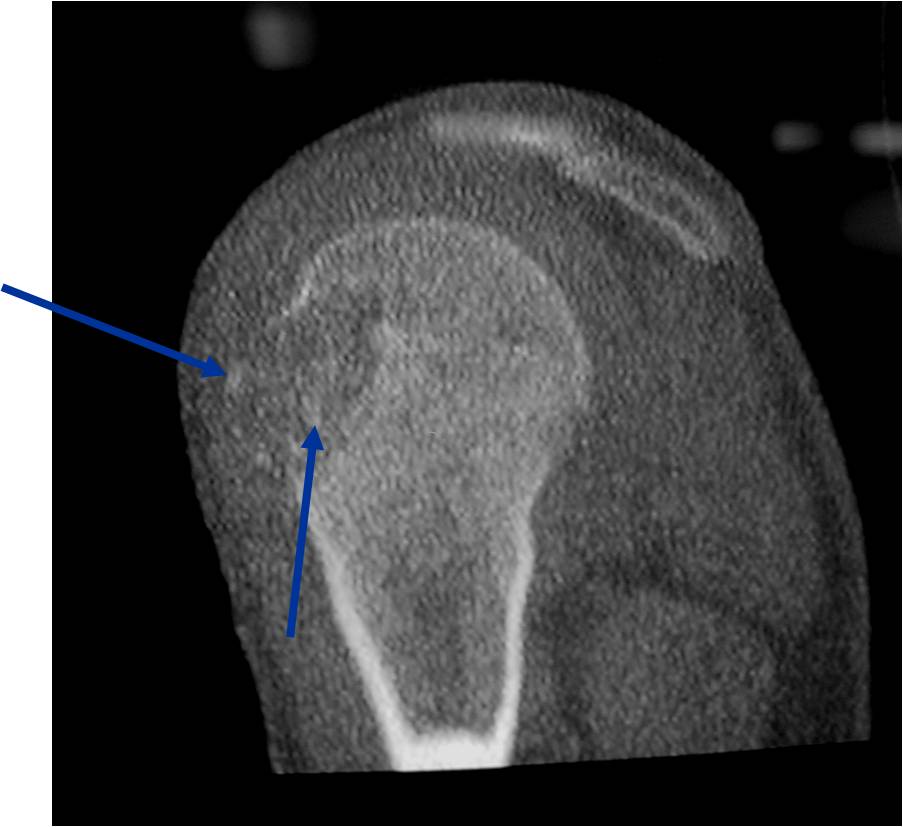

Radiographic Presentation

- Presents as a highly defined/well circumscribed geographic oval/round lytic defect

- Surrounded by rim of sclerotic bone

- Usually in epiphyseal region

- Lesion ranges from 3 cm to 6 cm diameter

- Usually radiolucent

- May have fine trabeculae and irregular calcifications

- Calcifications are often better detected with a CT scan but are not uniformly present

- Lesions may expand the bone and new periosteal bone may form

- Bony end plate, cortex, bone contour are unaffected